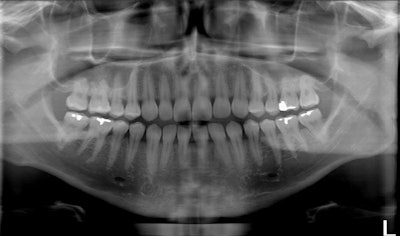

Standard panoramic image from a PC-1000 system using a CdTe sensor from Ajat, self-corrected with tomosynthesis software. Images courtesy of Dr. Robert Langlais.

The tomosynthesis software then autocorrected the image to bring the front teeth into focus.